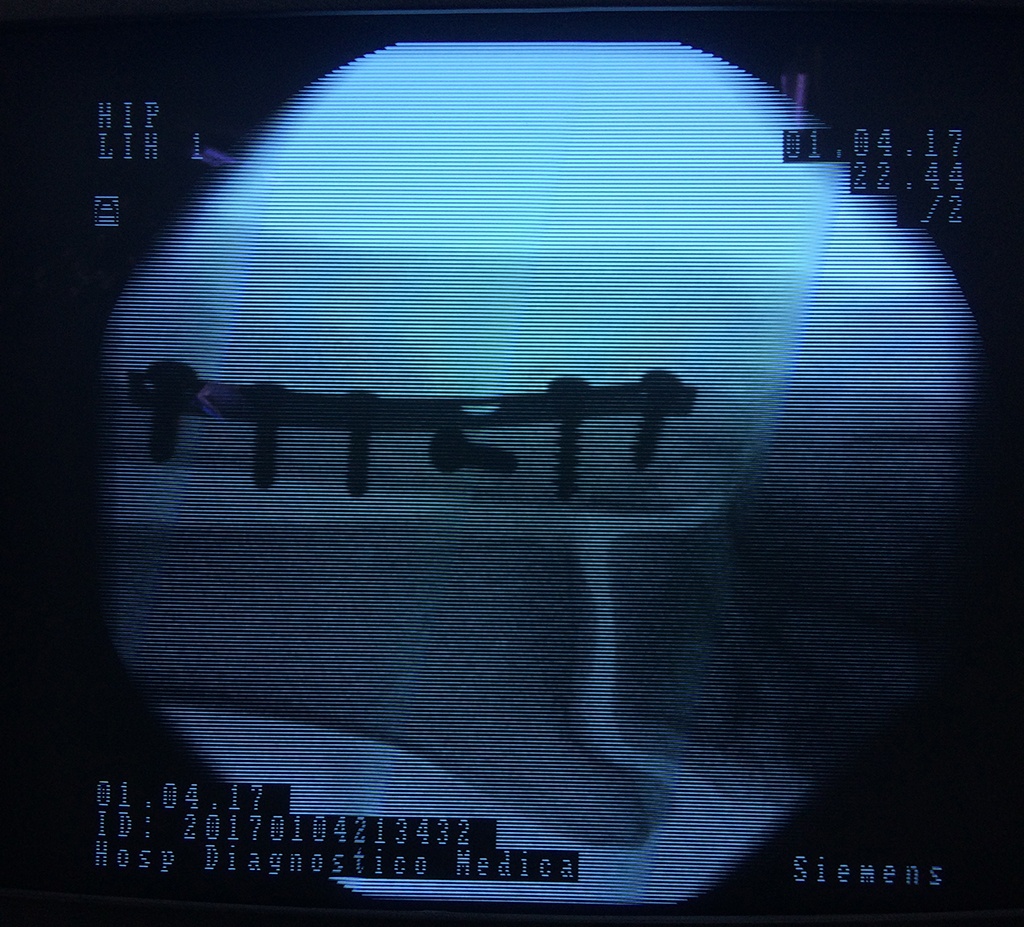

Cirugías de Tobillos

Cuando se necesita cirugía, es probable que esta implique el uso de clavijas de metal, tornillos o placas para sostener los huesos en su lugar mientras la fractura se consolida. Los elementos de soporte pueden ser temporales o permanentes.